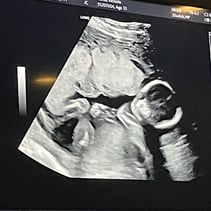

Greetings! I’ve been away from my updates for a couple of weeks, so lets get you caught up on all the things! First off, we had our Anatomy Scan today and hit the half way mark of the pregnancy. WOW. Our baby girl is doing so so well. From head to toe, she’s about 9-10inches and weighs 12oz. A week or two ago I stopped having all pregnancy symptoms besides the obvious physical changes. This was awesome but also made me a little uneasy. I also have not felt much movement and waiting 4 weeks for my 20 week appointment was starting to make me very antsy in a horribly, anxious way. Having a miscarriage the first time around has really made it difficult to relax and feel confident that everything is going well. Last week Steven went ahead and bought me a Doppler to listen to our baby’s heart beat at home while we waited for our next appointment. Once it came in and I found that wonderful sound of her heart, whew! Instant relief. Today was even better! Not only is SHE healthy, but so am I! I started going to the gym a few days out of the week and signed myself up for a 4 week Prenatal Yoga class that takes place every Saturday. My blood pressure today was 118/72 and weighing 129 which is 4 pounds more than my last appointment. I feel wonderful and even more excited than I was before to meet our girl! We’ve started clearing out the room that will be her nursery and are so grateful to the friends and family that have already started pouring their love into us and our baby with the registry gifts! Steven also surprised me with setting me up to visit family in Texas next month during my Spring Break from work. What a guy. 💕 I hope you all enjoy these photos! You‘ll see her profile with her cute little nose! There’s one of her foot, one of her crunched up with her legs bent, a crazy one of her that looks like a Halloween photo, and it’s hard to tell but one of her lips and nose. She was spinning and drinking and kissing us while she was having her first photoshoot. I will start feeling her more in the next couple of months. I have an anterior placenta so it makes things a little harder to feel since its placed in the front of my uterus. She is having fun, nonetheless. That’s all for now! We love you aaalllllll. A note from Steven: we could clearly tell during the sonogram that she gets her dance moves from her daddy.